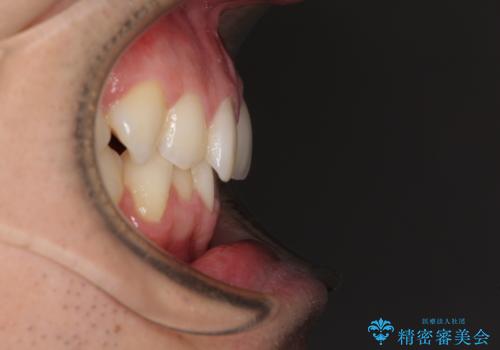

ディープバイトと叢生 インビザラインによる矯正治療

- 前歯のディープバイトと叢生を気にして来院された患者様です。

上下ともに叢生が認められたため、親知らずすべてを抜歯し、歯列全体を後方へ移動させることで歯列を整えることとしました。

ディープバイトもデコボコも改善され、気になっていた銀歯もセラミックとなり、患者様には大変満足していただきました。